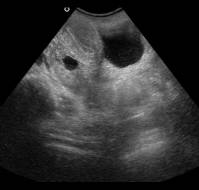

Smaller ovarian cysts smaller than 3 cm resolve faster than cysts that are larger than 6 cm, suggests a study published in the journal Obstetrics & Gynecology.1Over ..

Ovarian cysts are frequently found incidentally during pregnancy and can pose significant diagnostic and management due to potential risks to both the mother and fet..

Ovarian cysts are frequently discovered during pregnancy and can pose diagnostic and management challenges due to potential impacts on both the mother and fetus. Thi..